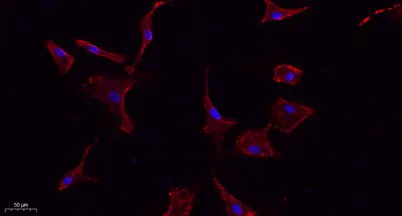

- Validated Applications: WB, IHC, IF, ELISA

- Dilution: Western Blot: 1/500 - 1/2000. IHC-p: 1:100-300 ELISA: 1/20000. IF 1:100-300 Not yet tested in other applications.